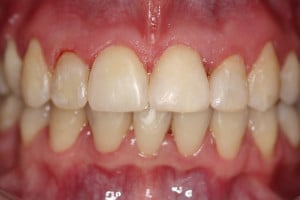

Młoda pacjentka zgłosiła się do naszego gabinetu celem wykonania kompleksowego leczenia zachowawczo-ortodontycznego. Oprócz problemów natury ortodontycznej stwierdzono złą higienę jamy ustnej oraz liczne potrzeby leczenia zachowawczo-endodontycznego. Po wnikliwej analizie telerentgenowskiej oraz analizie modeli zadecydowano o ekstrakcji 2 zębów w łuku dolnym (kła po stronie lewej oraz pierwszego przedtrzonowca po stronie prawej). Plan leczenia obejmował ponadto zamknięcie łuku po brakujących zębach w łuku górnym. Leczenie aktywne trwało 2 lata i 8 miesięcy. W czasie jego trwania pacjentka była regularnie poddawana zabiegom higieny profesjonalnej celem eliminacji zapaleń przyzębia brzeżnego. Po leczeniu aktywnym zastosowano leczenie retencyjne w postaci retainera stałego w żuchwie oraz szyny retencyjnej w łuku górnym.